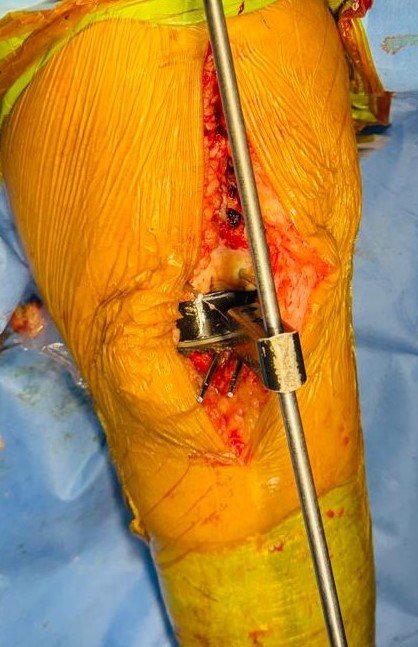

Intra-Op (Photos)

Stiff Knee with Flexion Contracture & Rigid Varus